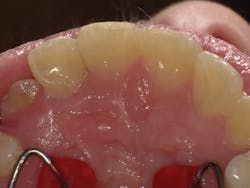

Figure 2

I'll demonstrate this material's versatility with a few cases. First is a large Class III cavity. The patient was extremely apprehensive, so we decided to prepare the cavity using the Lite Touch (AMD Lasers) erbium YAG laser. Very often, as in this case and the next few cases that we will depict, cavity preparation can be performed without anesthetic. In Figure 1, we see the preoperative image of the large Class III cavity on tooth No. 8. Using the Lite Touch laser (figure 2), we were able to excavate the entire cavity in a clean and efficient manner (figure 3). Using a fine diamond, a slight bevel was completed on the enamel at the cavo surface margin. By beveling the enamel, we improve the bond of the adhesive and allow for a seamless blend of the restorative material to the outer tooth structure. In deep restorations such as this, a calcium liner can help minimize sensitivity and act as a buffer between the restoration and pulp. Both Calcimol LC (Voco) and Theracal (Bisco) can be used in this manner. In this case, we decided to use Theracal. Theracal was placed in the deepest area and light-cured for 15 seconds (figure 4). After a 37% phosphoric acid etch of the enamel margin, we applied Futurabond U (Voco) as per the manufacturer's instructions and light-cured for 10 seconds. Admira Fusion shade A2 was placed in three increments and polished. The final restoration exhibits a beautiful luster and a seamless blend from the restoration to the natural tooth (figure 5).